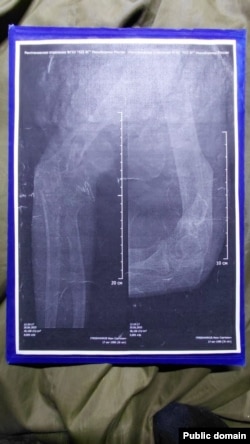

Снимки сломанной руки Ивана Гребенникова

– Нам казалось, что после возвращения из плена нас хотя бы лечить будут. Куда там – нам в наглую поменяли категории на фальшивые – мне, например, мою "Д" заменили на "Б" (годен к службе с незначительными ограничениями), хотя у меня правая рука как была в нескольких местах перебита – так и висит. У меня до сих пор пуля в теле – даже не оперировали, – говорит Иван. – И нас таких очень много – на костылях, в гипсе. Им просто по**й, везут на Донецкое направление калек.